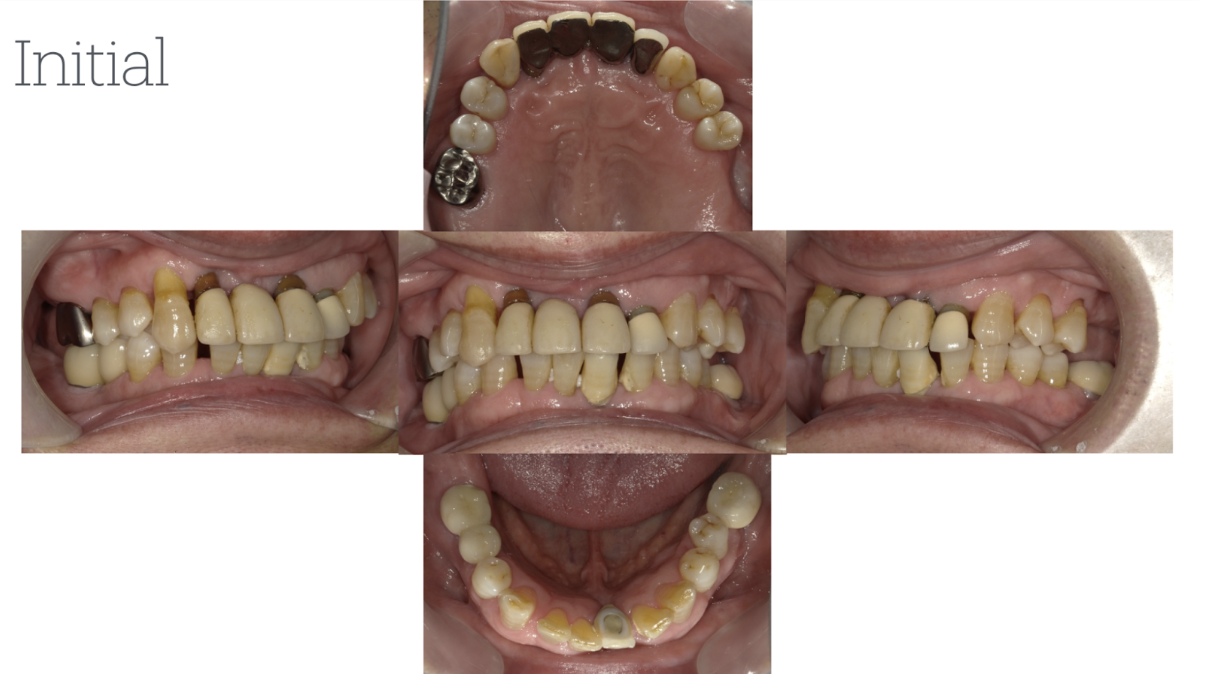

患者3

年齢性別:60代女性

主訴:以前より、見た目の改善を含め、奥歯の摩耗が気になっており治療を希望。

まずは、矯正治療にて歯のポジションを改善。その後、インプラントと金属の除去にて回見合わせを最終調整。全体的な噛み合わせが改善し、歯軋りも気にならなくなったとのこと。現在、定期検診を継続中。